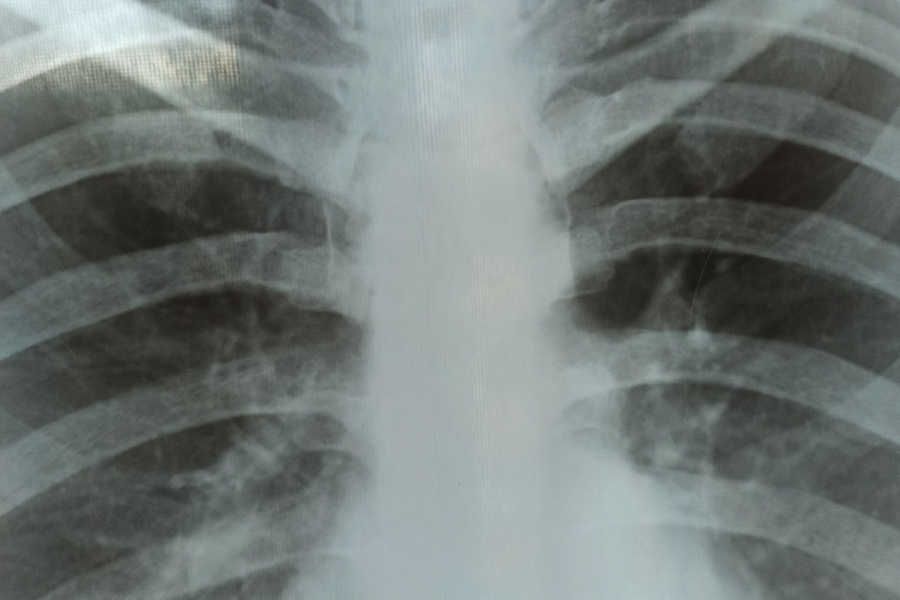

- онкоскрининг для определения образований легких проводится посредством флюорографии легких для граждан в возрасте 18 лет и старше с периодичностью 1 раз в 2 года. Многие тяжелые, смертельно опасные болезни, в том числе рак легких и туберкулез, длительное время могут протекать скрытно, без видимых изменений самочувствия больного. И только регулярные прохождения флюорографического обследования позволяют выявить болезнь своевременно, на ранних стадиях. Это позволит полностью излечить заболевание, вернуть здоровье, а с ним и привычные режим и стиль жизни.